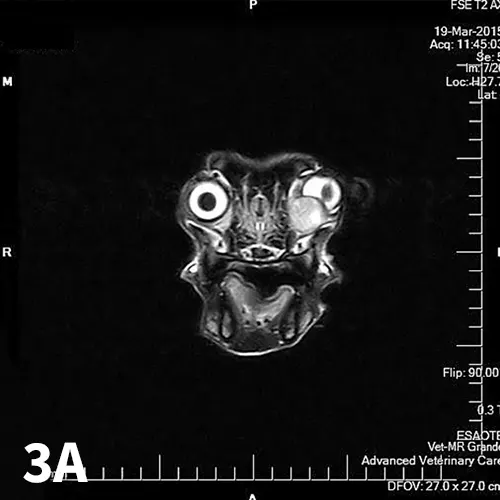

FIGURE 3

(A) Axial T2-weighted and (B) sagittal T2-weighted postcontrast MRI images of the dog in Figure 1 with a mixed orbital carcinoma. Note the lobular mass ventromedial to the left eye. It is causing dorsolateral distortion of the ventral globe.

Orbital neoplasia (Figure 3) can be classified as primary (involving the orbital tissue directly) or secondary (arising from a distant site or extension of a contiguous structure). Approximately 90% to 95% of all orbital neoplasias are malignant in the dog and cat,2 with 92% and 58% being primary in the dog and cat, respectively.5 Orbital neoplasias are usually associated with slowly progressive exophthalmos and minimal pain, although approximately one-third of orbital neoplasias are painful.2 MRI or CT is used to localize and define the margin of orbital tumors. Usually, excision of these tumors is not curative. Orbital exenteration—removal of all orbital contents, including the globe—is advised, even in a visual eye. Consultation with a veterinary oncologist for potential chemotherapy or radiation therapy is strongly recommended owing to the aggressive, malignant nature of these tumors.1-3,5